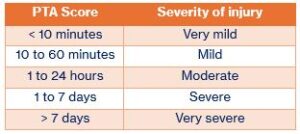

When someone experiences a traumatic brain injury (TBI), they might go through a phase of recovery called Post-Traumatic Amnesia (PTA). This is a period when they will feel confused, forget things that just happened, or not remember where they are of what day it is. PTA can last minutes, hours, or weeks which is normal for the stage of recovery.

The length of PTA helps doctors understand how serious the injury may be and what kind of support the person might need.